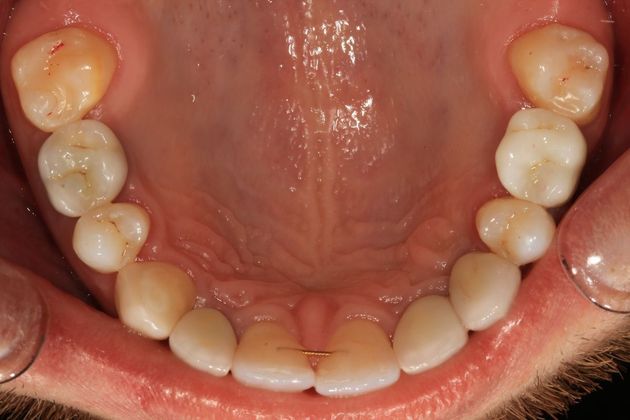

Full mouth rehabilitation. This 20 year old patient had emigrated from Bosnia only a few years earlier with his mother and two sisters after his father had perished in the Bosnian/Serbian conflict. He had severe hereditary dental dysplasia, with multiple retained baby teeth where permanent teeth never formed. He had a total of nine missing teeth, and the teeth that were present were not in their correct positions, leading to a poor bite relationship and multiple large gaps throughout his mouth. He was embarrassed to smile and wanted to know what could be done. His was a very complex case requiring Smile design and; the services of an oral surgeon to take out the baby teeth and strategically place implants at different times of his treatment, an orthodontist to level, straighten and create the proper size spaces for the placement of nine implants, gum sculpting, whitening, and the placement of fillings and crowns on natural teeth, and crowns on the nine implants. It took some time, but he got a great result and the resulting confidence has helped him go to college, get a better job and have a social life! Procedures: Smile design, oral surgery and implant placement, orthodontics, gum lift, whitening, fillings and crowns. TESTIMONIAL:" Dr. Balloch is a very skilled, compassionate and empathetic dentist who develops a personal relationship with his patients. He is (by far) the best dentist that I have experienced in my 85 years. His dental and office staff are equally friendly and professional. Dr.Balloch definitely exceeded my expectations. I highly recommend!"